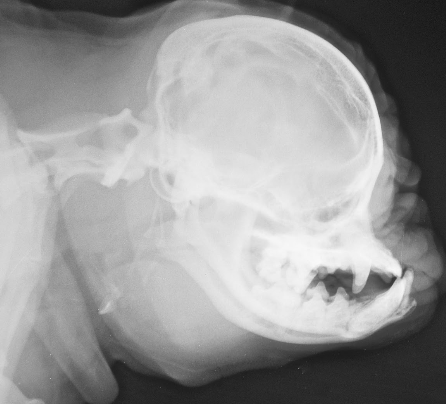

In a new study published today in the journal PLOS ONE, scientists from the University of Surrey, working with an experienced breeder in the Netherlands, examined how the skull and brain of toy dogs change when a Brussels Griffon with is crossed with an Australian Terrier. The succeeding hybrid puppy is then back crossed to a Brussels Griffon to give some of the features of the Brussels Griffon, but keeping the longer skull of the Australian Terrier.

The results from the study showed it is possible to breed a dog which had the external features of a short-nosed Brussels Griffon and reduce the risk of Chiari malformation, a debilitating condition found in toy dogs and affecting 1 in 1,280 humans. The disease is characterised by premature fusion of skull bones forcing parts of the brain to push through the opening in the back of the skull causing fluid filled cavities to develop in the spinal cord. Chiari malformation causes headaches, problems with walking or even paralysis and has become prevalent in some toy breed dogs as a result of selective breeding.

The breeder, Henny van der Berg, proposed the project idea after an accidental mating between two of her dogs. The four-year study analysed five traits on magnetic resonance images (MRI) scans and how they changed generation by generation in the family of 29 dogs. Using a careful selection of head shape and MRI scans over two generations, the findings revealed it was possible to breed a dog which had the external features of a Brussels Griffon, but is less susceptible to Chiari malformation.